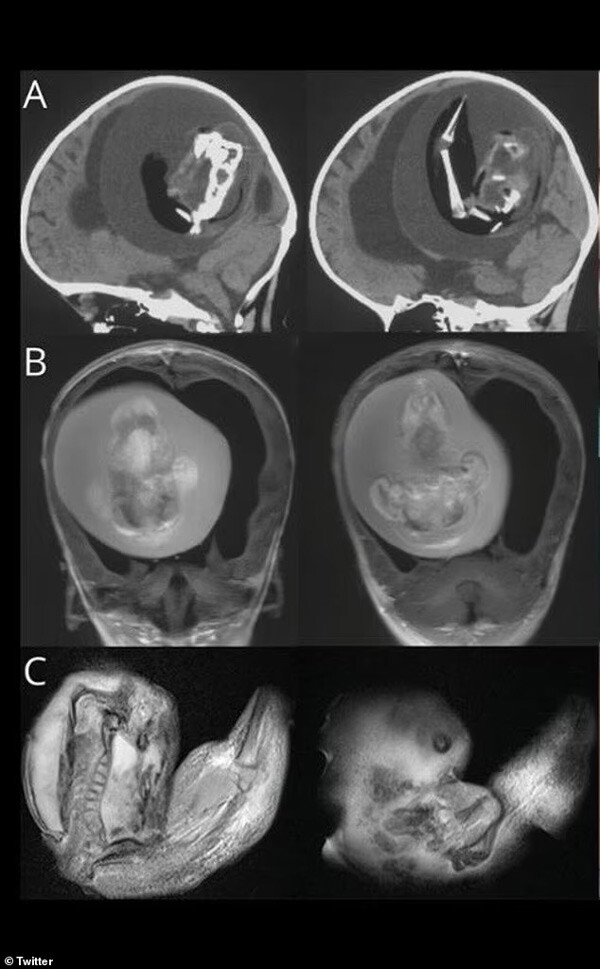

Daha önce sadece birkaç kez kaydedilen tıbbi anomalide, 1 yaşındaki kız çocuğunun beyninden doğmamış ikizi çıkartıldı. Bebeğin beyin ameliyatı Şanghay'daki Fudan Üniversitesi'ndeki doktorlar tarafından gerçekleştirildi.

Yaklaşık beş santim uzunluğundaki fetüsü doktorlar, anne babanın kızlarını kafası büyüdüğü ve motor becerilerinde sorunlar yaşadığı için hastaneye götürdüklerinde fark etti.

Nadir görülen vaka, Aralık ayında Amerikan Nöroloji Akademisi'nin Neurology dergisinde açıklandı. İsmi gizli tutulan kız çocuğu, motor becerileriyle ilgili sorunlar göstermesi üzerine hastaneye kaldırıldı. Tomografi taramaları, doğmamış kardeşinin beynine baskı yaptığını ortaya çıkardı.